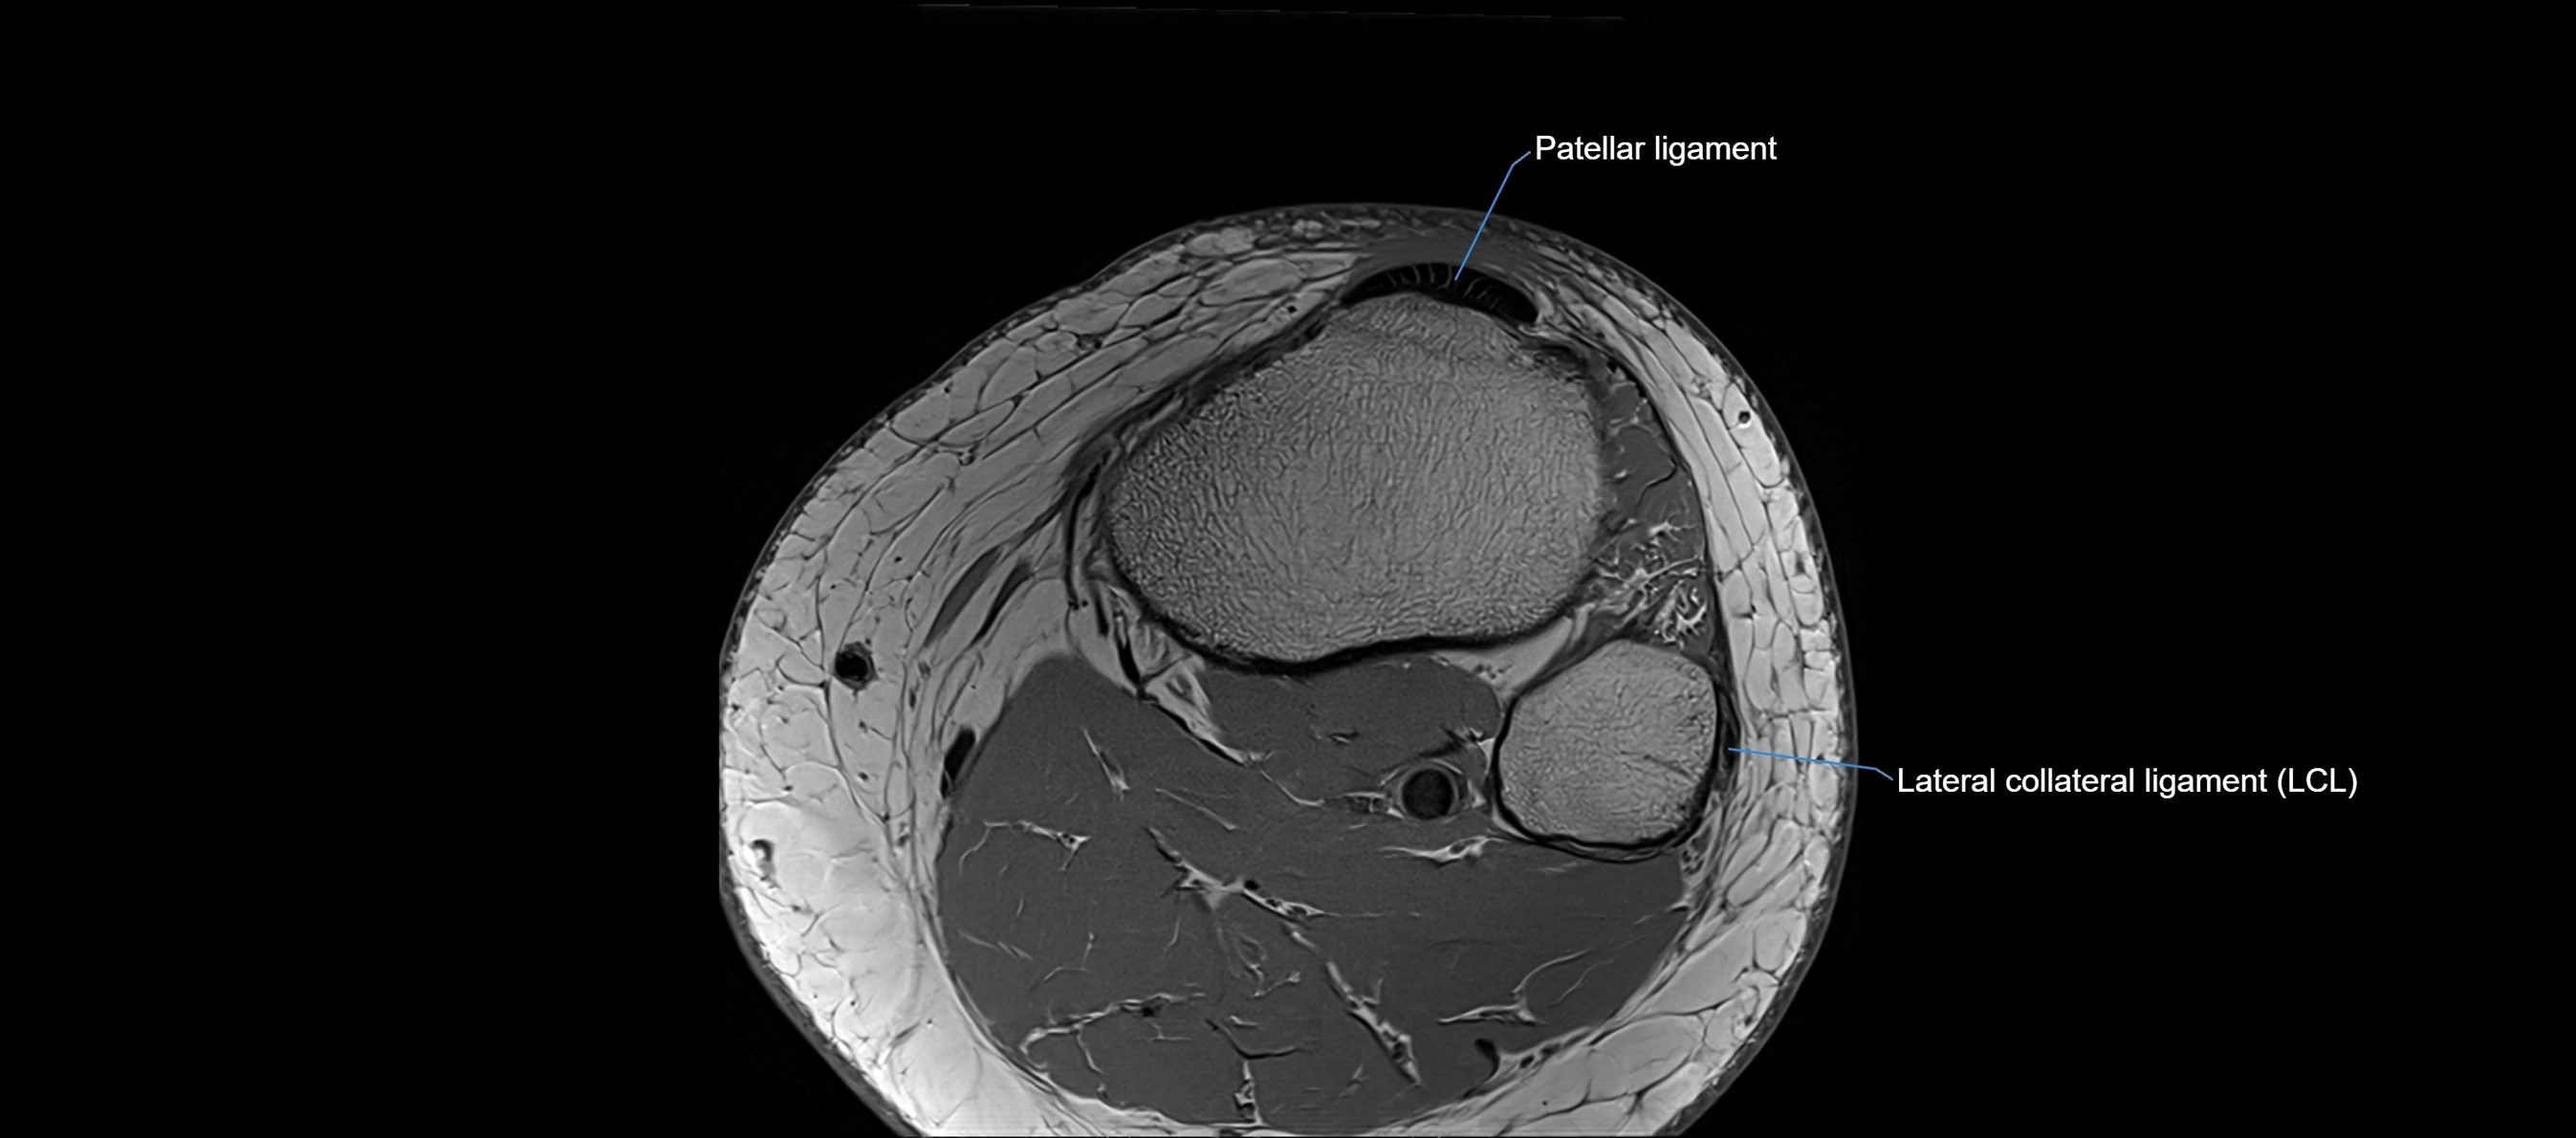

MRI images

image